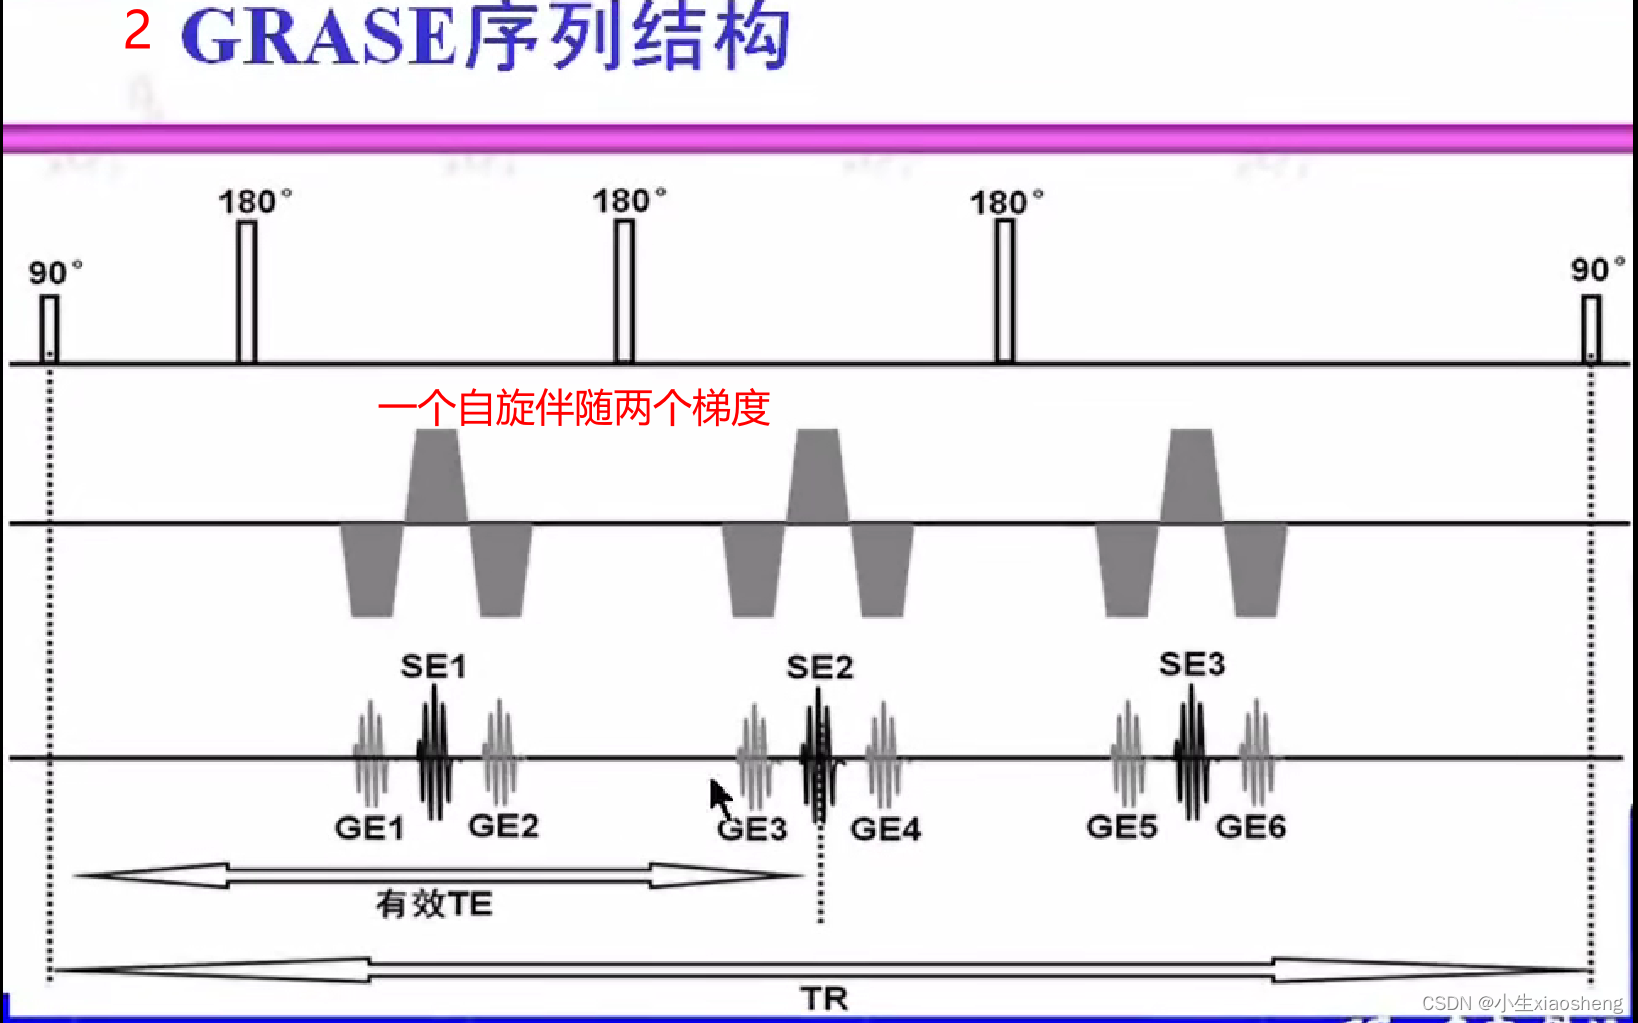

自旋回波--90度和180度填充K空间;反转恢复--在自旋的基础上两边加180度;梯度回波--消除每次脉冲留下的影响,以及波的次数;propeller==》K空间填充技术和FSE或FIR结合用于减少运行伪影;EPI==》采集方式,一次激发采集多个回波的形式但与单次不一样;PRESTO和GRASE==》前面几种的一种结合形成新的。

八、PRESTO和GRASE序列